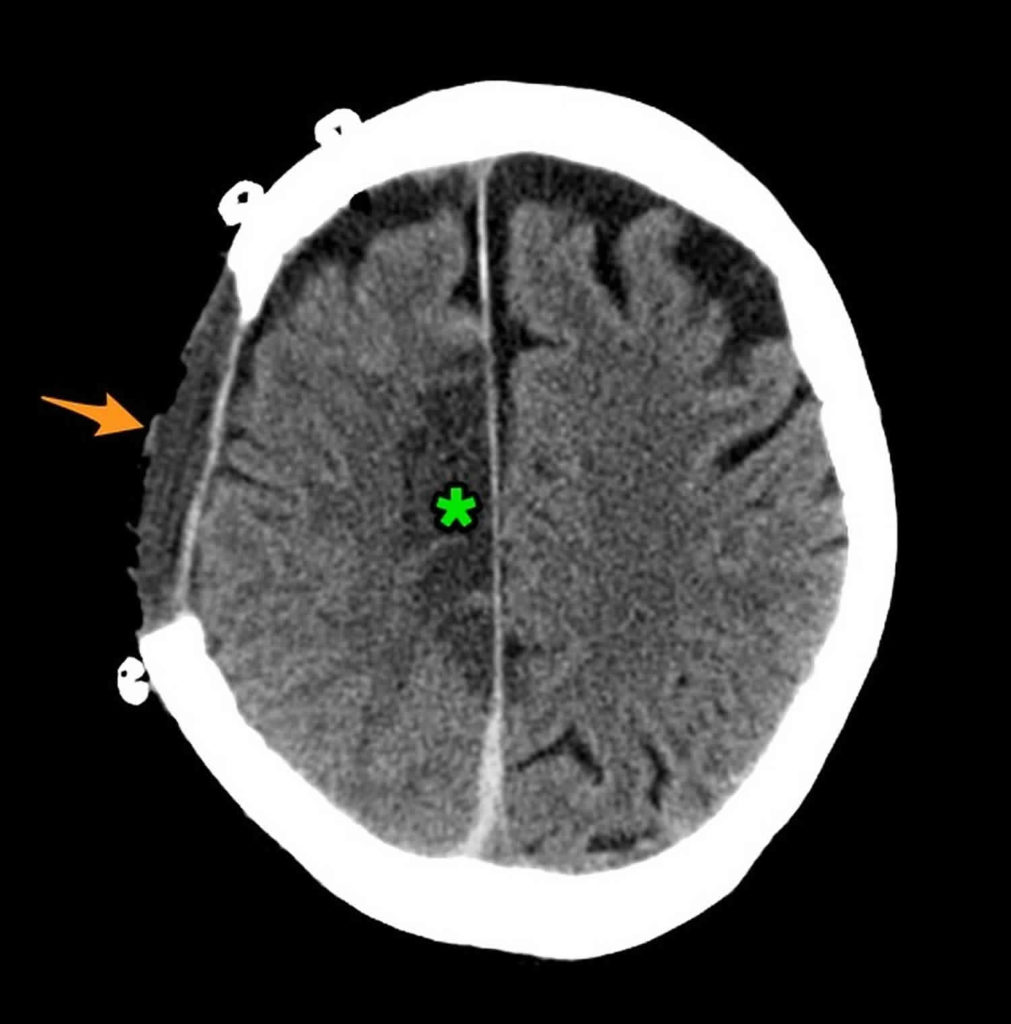

Bleed with a midline shift….s/p fall on thinners r/Radiology What Is A Midline Shift Of The Brain Midline shift describes the situation where the midline of the intracranial anatomy is no longer in the midline and is the result of pushing or pulling forces within. But what exactly is this midline, and why is it so crucial to our brain’s. Midline shift refers to a shift (displacement) of brain tissue across the centre line of the brain.. What Is A Midline Shift Of The Brain.

CT brain hemorrhage What Is A Midline Shift Of The Brain Especially for operating on a mass or lesion or evacuating brain hematoma. Midline shift refers to a shift (displacement) of brain tissue across the centre line of the brain. Midline shift describes the situation where the midline of the intracranial anatomy is no longer in the midline and is the result of pushing or pulling forces within. It may occur. What Is A Midline Shift Of The Brain.